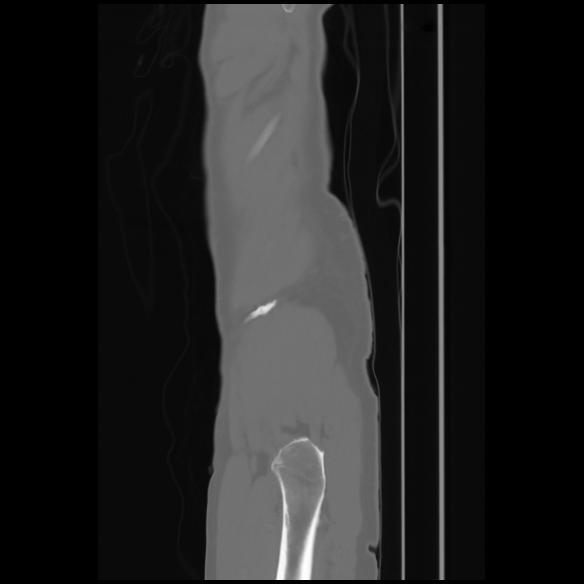

7 CUERPO,CE,Sagittal,3.000,CUERPO,Sagittal,